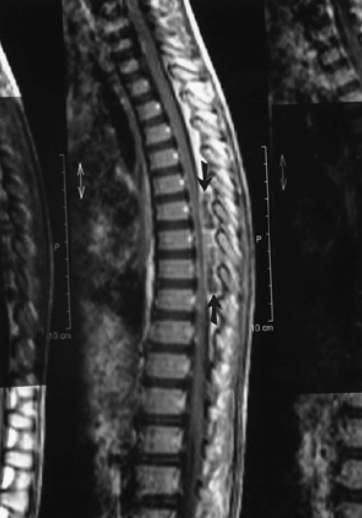

What imaging is useful in dx of epidural abscess?

MRI w gadolinlium